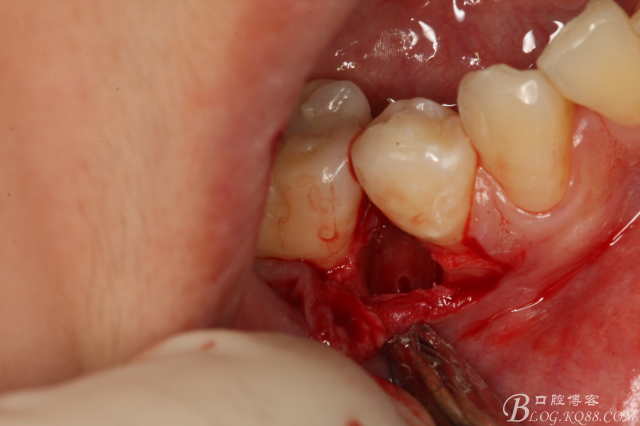

圖16.取出45牙根,牙槽窩完整、不變形。

圖17.清理牙槽窩,切口止于膜齦聯(lián)合處,這樣術(shù)后不腫脹。

圖18.放膠質(zhì)銀

圖19.縫合

圖20.拔除的45牙根。